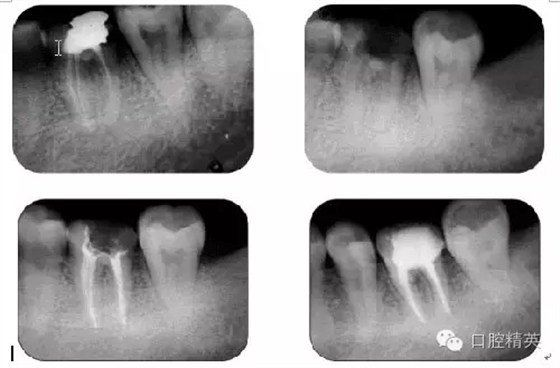

病例3:C型根管

病例5:遺漏根管再治療